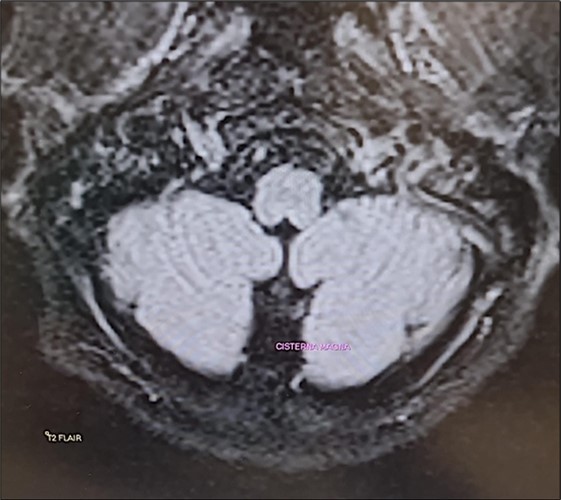

The Epley maneuver was performed with immediate effect (third evaluation; video 2). In fact, unsteadiness was reduced and gait was possible without assistance. Mild dysmetria remained in the finger-to-nose test. The intention tremor of the arms was almost completely resolved. Laboratory tests still showed hypomagnesemia (1.1 mg/dL) and hypocalcemia (7.5 mg/dL). Twenty-four-hour urinary magnesium was 9 mg (normal 73-122 mg). A new brain MRI confirmed the same findings as the previous one (Figure 1). Given the clinical improvement, intravenous magnesium sulfate supplementation was discontinued and daily oral magnesium citrate supplementation (1200 mg/d) was started. Cinnarizine-dimenhydrinate was discontinued, while the patient was advised to take l evosulpiride as needed. Follow-up was scheduled in 7 days or earlier if there was a change in clinical status.

Figure 1.Transverse section of brain MRI (T2 Flair) showing absence of cerebellar edema.

It is important to note that although the literature almost always reports MR-documented cerebellar edema18associated with hypomagnesemia, we did not observe the same finding in our patient in two consecutive brain MRIs performed approximately 15 days apart. It is possible that, although the authors do not specify the time at which this evaluation was performed in their patients, it was done at a stage in which hypomagnesemia had been present for some time. In our case, however, a very pronounced hypomagnesemia had developed hyperacutely, and perhaps the cerebellar edema described by other authors had not yet had a chance to develop. To the best of our knowledge, the case of a cerebellar syndrome induced by acute hypomagnesemia as a result of a benign and peripheral disease, has not been described.

The case we present is special for the twofold reason that it shows how the most “benign” cause of vertigo can be complicated by massive neurovegetative effects and cause a severe cerebellar syndrome induced by acute hypomagnesemia and also because, unlike previous reports in the relevant literature, a hypomagnesemia-induced cerebellar edema was not highlighted.